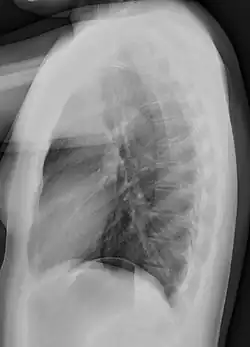

Chest film showing increased opacity in both lungs, indicative of pneumonia -